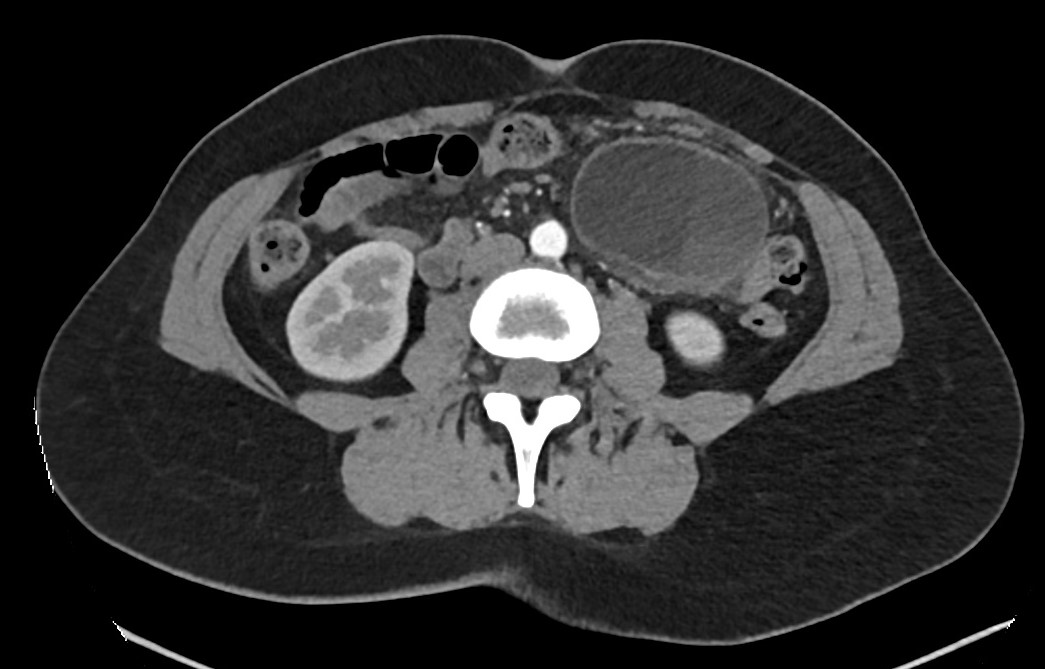

Hallazgos ecográficos

Ecografía abdominal en el Centro de Atención Primaria: lesión quística anecoica de 80 x 46 x 54 mm ubicada en mesogastrio. Quiste complejo de 30 x 30 mm, de paredes y septos engrosados, ubicado en polo superior del riñón izquierdo.

Juicio clínico: hallazgos de una lesión quística en mesogastrio y otra lesión quística compleja en el polo superior del riñón izquierdo.

Tomografía computarizada de abdomen: lesión quística en flanco izquierdo sin evidente dependencia con ningún órgano y de probable origen mesentérico o mesenquimal, posible linfangioma. Cambios inflamatorios periféricos y contenido heterogéneo post-sangrado. Quiste renal izquierdo Bosniak tipo III.

Resonancia magnética intestinal y renal: lesión mesentérica de 7,3 cm compatible con linfangioma quístico versus quiste dermoide. Quiste cortical en el polo superior del riñón izquierdo Bosniak III.

Evolución: La paciente es intervenida quirúrgicamente con exéresis del quiste mesentérico y nefrectomía izquierda parcial.

Resultados de anatomía patológica: pseudoquiste mesentérico sin evidencia de malignidad y carcinoma renal de células claras.